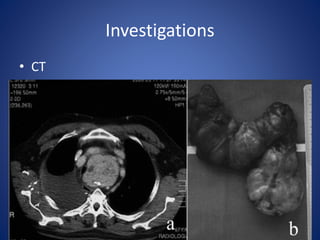

Investigations

• CT